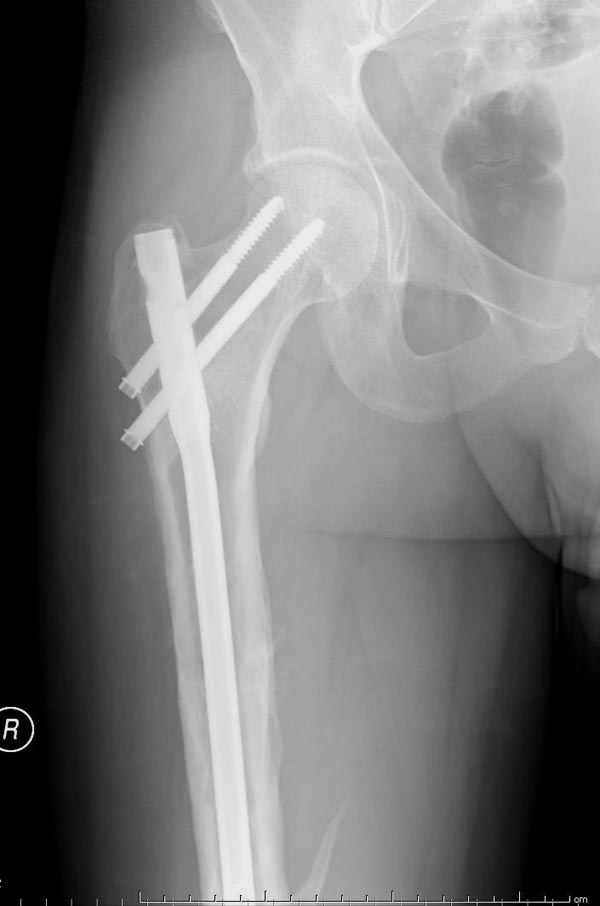

Рутинный интрамедуллярный остеосинтез с расверливанием и с фиксацией реконструктивным трокантерик штифтом (рис №1, №2),

если первые 4 месяца послеоперационного периода проходил без проблем, но на 5 месяце появились боли в дистальном отделе бедра и температура, т.е. симптомы медуллярного инфицирования (рис №3, №4).

При обзоре причин перелома, на снимке №2 обнаружили, что один из стержней аппарата наружной фиксации проходил только через передний кортекальный слой, что создало стрессовую зону на бедре и в результате перелом из-за незначительной травмы.